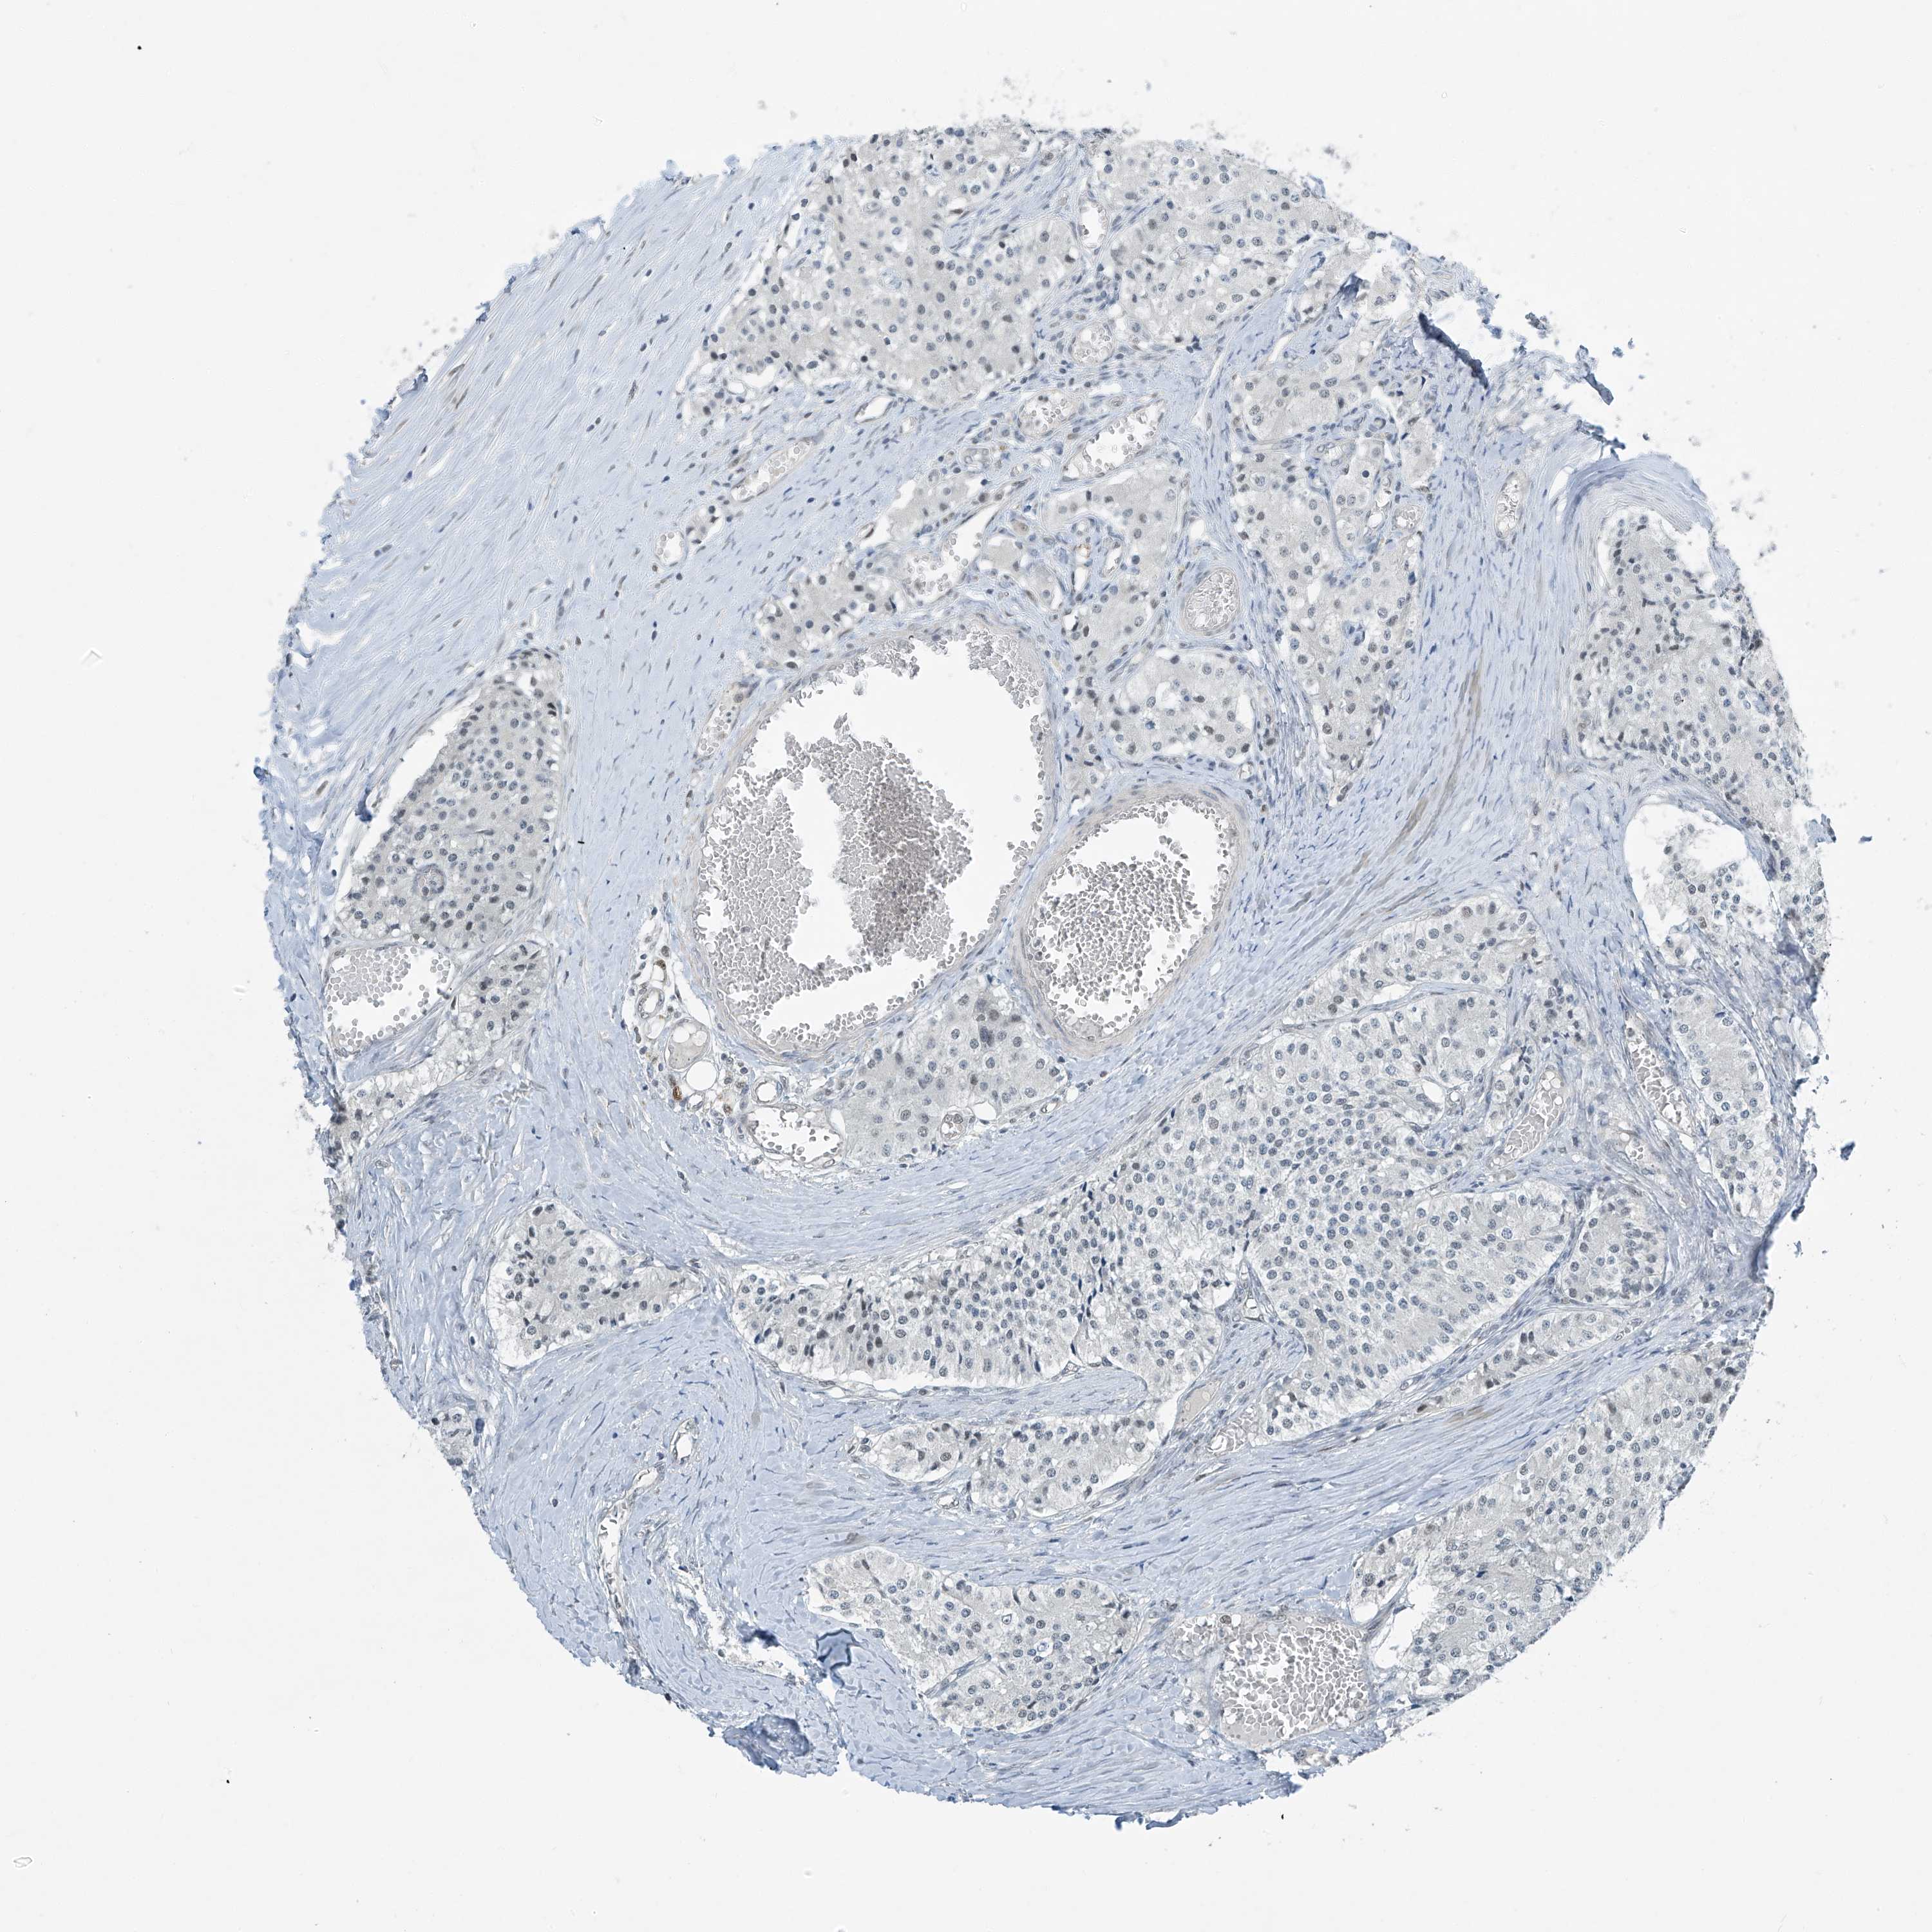

CARCINOID - Protein expressioni

A mouse-over function shows sample information and annotation data. Click on an image to view it in a full screen mode. Samples can be filtered based on level of antibody staining by selecting one or several of the following categories: high, medium, low and not detected. The assay and annotation is described here.

Each image is clickable and will lead to virtual microscopy that enables deeper exploration of all samples and also displays staining intensity scores, fraction scores and subcellular localization as well as patient and tissue information for each sample.

Antibody HPA031730

Staining

High

Medium

Low

Not detected

Intensity

Strong

Moderate

Weak

Negative

Quantity

>75%

75%-25%

<25%

None

Location

Nuclear

Cytoplasmic/membranous

Cytoplasmic/membranous,nuclear

Carcinoid, malignant, NOS